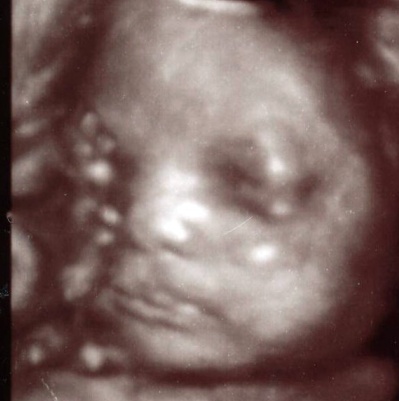

Mit unserem hochmodernen Ultraschallgerät verfügen wir über die modernste Ultraschalltechnik, die derzeit überwiegend in der Geburtshilfe genutzt wir, nämlich dem dreidimensionalen Ultaschall, welche sogar auch die Bewegung, also 4-dimensional, darstellen kann. Unter günstigen Bedingungen gelingen eindrucksvolle, plastische Aufnahmen, z.B. des kindlichen Gesichts bei bestimmten Fragestellungen. Technisch besteht die beste Gelegenheit für 3-D-Ultraschall-Untersuchungen zwischen der 20. und 30. SSW. Die Qualität der Aufnahmen hängt sehr von der kindlichen Lageeinstellung, der das Kind umgebenden Fruchtwassermenge sowie vom mütterlichen Gewicht ab.